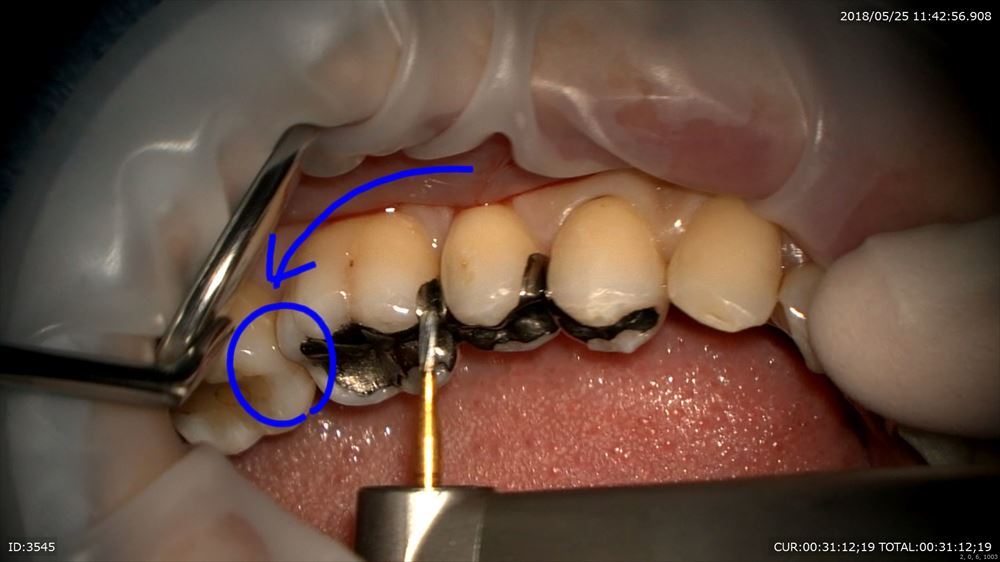

次のケースは左下に違和感があり咬むと痛い

咬むと痛いときはヒビやクラックが原因という事が多いです。金属の下の虫歯だけでなく

実はマイクロスコープを使用してこんな所を観察

ここにも原因があったのです。